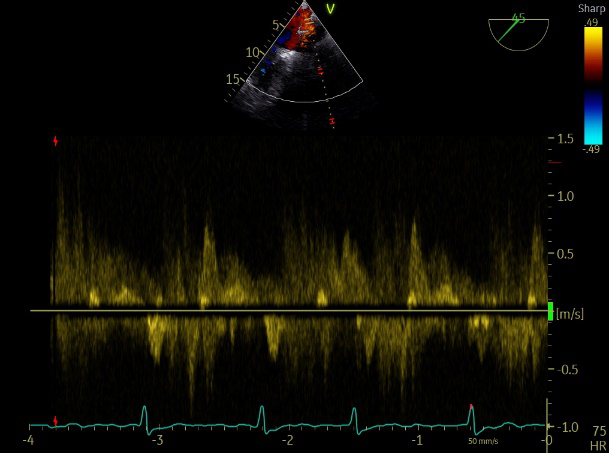

肺静脉血流频谱呈收缩期反向

患者麻醉方式为全麻,建立静脉通路后,穿刺右侧股静脉,预埋ProGlide缝合器,食道超声指导下房间隔穿刺成功,将Superstiff导丝送至左房,应用18F鞘管扩张穿刺部位,沿导丝将导引导管送入左房,MitraClip调整后顺利到达二尖瓣目标位置,在X线及食道超声辅助下,将Mitraclip NTR成形夹精确定位后,成功夹合二尖瓣A2-P2区,超声显示反流明显减少,多切面证实夹合组织充分,肺静脉多普勒波形由反向恢复正常,手术顺利结束,安返普通病房。

术中超声

3D-color:残余少量返流